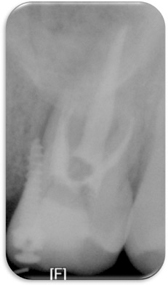

Figure 1

Pre-operative clinical photo.

Figure 1 Pre-operative clinical photo.